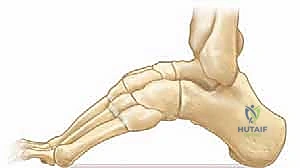

تُعد القدم الجوفاء عند الأطفال إحدى أكثر حالات تشوهات العظام تعقيدًا في مجال جراحة عظام الأطفال. لا يقتصر تأثير هذه الحالة على المظهر الخارجي للقدم، بل يمتد ليؤثر بشكل جذري على الميكانيكا الحيوية لحركة الطفل، وقدرته على المشي، ومشاركته في الأنشطة الرياضية واليومية. تتميز هذه الحالة بارتفاع مفرط في القوس الطولي للقدم، مما يؤدي إلى تركز وزن الجسم بالكامل على الكعب ومقدمة القدم (رؤوس الأمشاط)، متجاهلًا منتصف القدم الذي من المفترض أن يمتص جزءًا كبيرًا من صدمات المشي.

هذا التوزيع غير المتساوي للوزن يسبب آلامًا مبرحة، وتكون مسامير اللحم (Calluses) القاسية، وصعوبة بالغة في ارتداء الأحذية العادية، فضلًا عن الالتواءات المتكررة في الكاحل نتيجة عدم استقرار القدم. إن فهم هذه الحالة، والوصول إلى تشخيص دقيق ومبكر، وتحديد الخطة العلاجية الفعالة، هي خطوات حاسمة لضمان نمو صحي للطفل وتجنيبه إعاقات حركية في المستقبل.

* قوس مرتفع بشكل ملحوظ: يظهر بوضوح حتى عندما يقف الطفل ويحمل وزنه على قدميه.

* تغير في نمط المشي: مثل المشي على الحواف الخارجية للقدم (Supination).